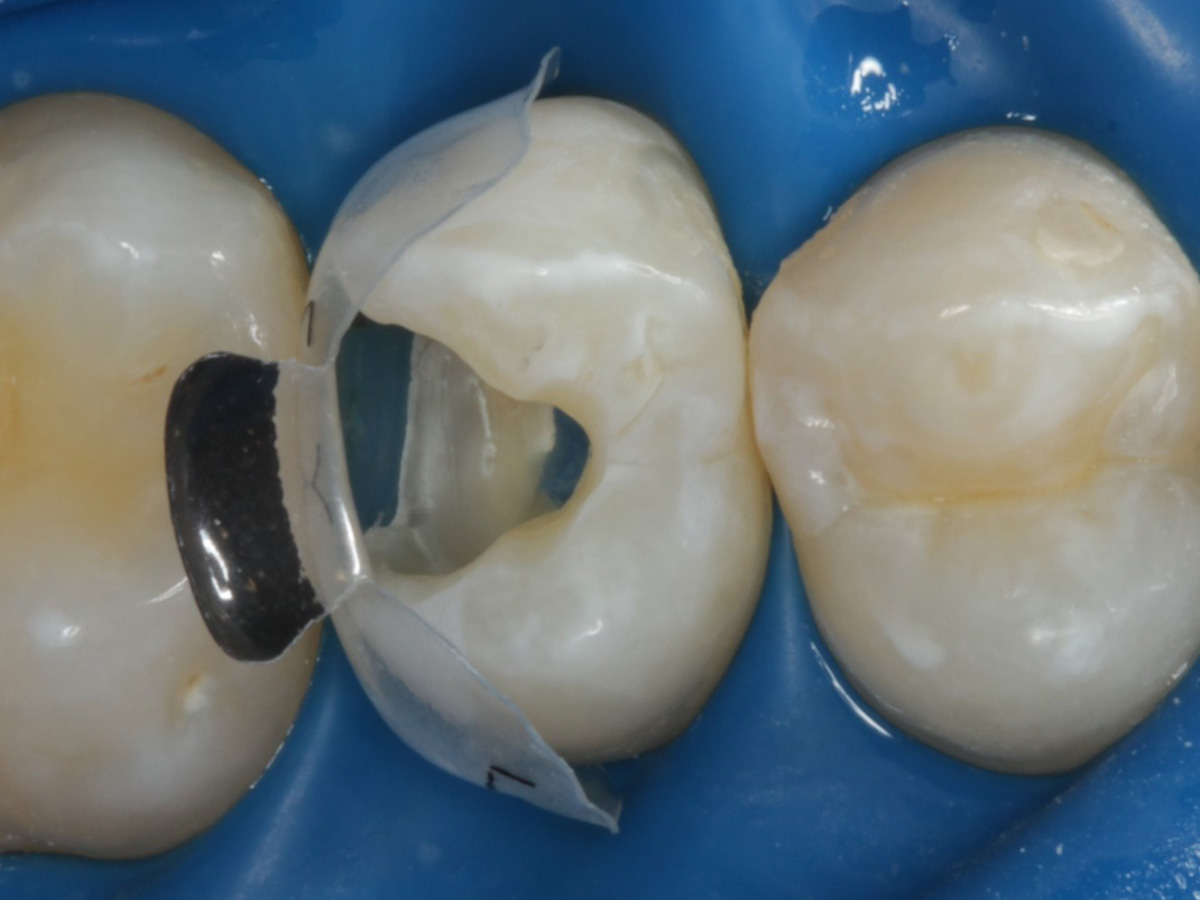

Abbildung 1

Bissflügelröntgenaufnahme, Approximalraumkaries an Zahn 25 distal

Abbildung 4

Schutz des Nachbarzahnes und des Kofferdams mit wiederverwandter Bioclear Biofit Matrize (gereinigt und sterilisiert)

Nach Applikation der Matrize: Evolve Schwarz Prämolar- 7 mm; Schmelzätzung

Nach Spray und Trocknung der Kavität: perfekte Adaptation der Matrize insbesondere tief subgingival